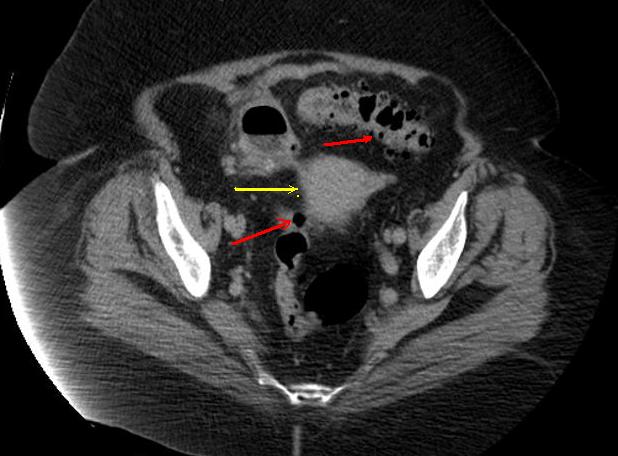

Aspect TDM du tuberculose ileocaecale est : Epaissisement

circumferentiel de la paroi ileum et caecum . Asymetrique

epaissisement de la valve ileocaecale .Mesenteric

lymphadenopathie et tuberculose pulmonaire est le plus

souvent .

Tuberculose ileo-caecale :

Image de epaissisement circumferentiele hyperdense

de ceacum avec lymphadenopathie mesenterique (

fleche rouge ). Image

TDM en coupe coronale |

Aspect de epaissisement

et stenosant de la paroi de ileon dans tuberculose

ileo-caecale( fleche rouge ) Image TDM en coupe axiale |